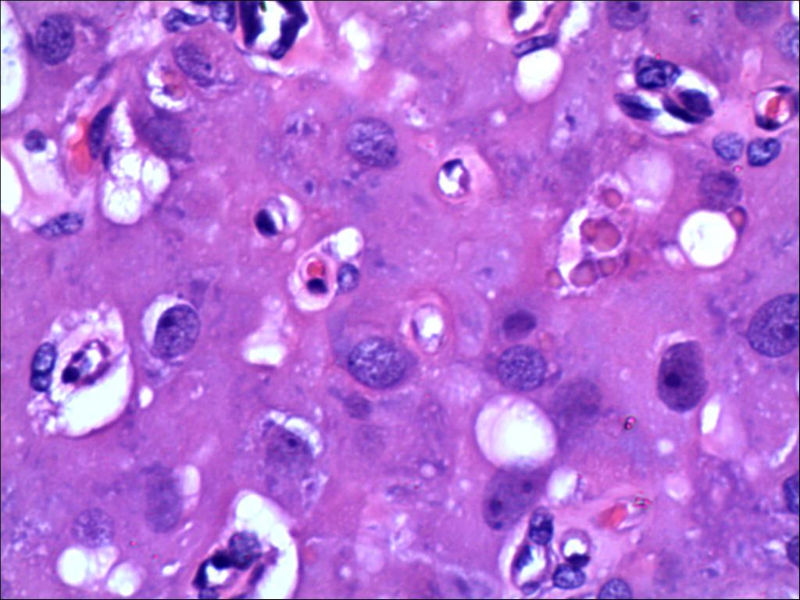

女,27岁,送检右侧卵巢肿物(另外还送检左侧卵巢肿物,大体及镜下显示为畸胎瘤),卵圆形,大小2×1×1cm,似有包膜。卵巢肿物图1

卵巢畸胎瘤中正常卵巢的黄体组织,铺砖样排列,胞浆宽大,较典型。

不好意思,可能是我没说清楚,患者对侧卵巢是畸胎瘤,不是同一侧的,我初步考虑门细胞瘤,图21,22,24,25,26中央的一些细胞是不是很像门细胞

谢谢大家的回答和解疑,忘记一个重要的病史,就是该女性为产妇。但是妊娠黄体瘤与类固醇细胞瘤怎么鉴别呢

那应该是妊娠黄体/黄体瘤,类固醇细胞瘤有嗜酸细胞和组织细胞样细胞两种,此例显然不是。